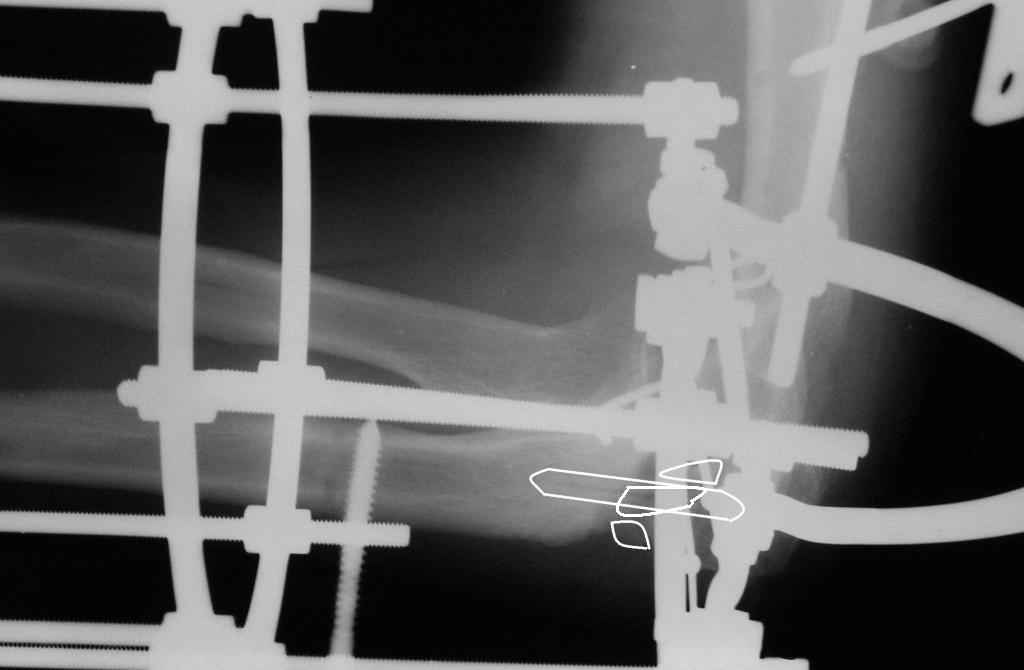

Через мыщелок плечевой кости проведен осевой трансоссальный стержень Штеймана. Аппарат изначально компоновался с возможностью восстановления движений в суставе. Через неделю после вправления попробовал разогнуть предплечье одномоментное на 10 град. - появилась сильная боль, предплечье стало стремиться в волярную сторону (вновь подвывих). Решил выполнить второй этап операции - костная аутопластика и остеосинтез, вероятно компрессионный в аппарате. С больным достигнута договоренность о длительном лечении в аппарате. Вправление предплечья, видимое на глаз, вселило в него надежду, что все идет по нашему с ним плану. Надеюсь в аппарате срастить и добиться движений. Опыт работы на локтевом суставе и аппаратами Волкова-Оганесяна, и Илизарова есть.

Коллеги! Сделана операция. Убрана рубцовая ткань, освежены концы до "кровяной росы", произведен релиз локтевого отростка и заднего отдела сустава - прошел до венечного отростка. После адаптации отломков выяснилось, что полное сопоставление происходит только на 1/4 периметра. Уложены аутотрансплантаты взятые из крыла подвздошной кости. Приведена схема. Через локтевой отросток проведены две спицы с упорными площадками с разбросом в 1 см, закрепленные на отдельном полукольце. Дана компрессия. Пятые сутки, рана заживает первичным натяжением. Выписываю. На 14 сутки буду пробовать движения.